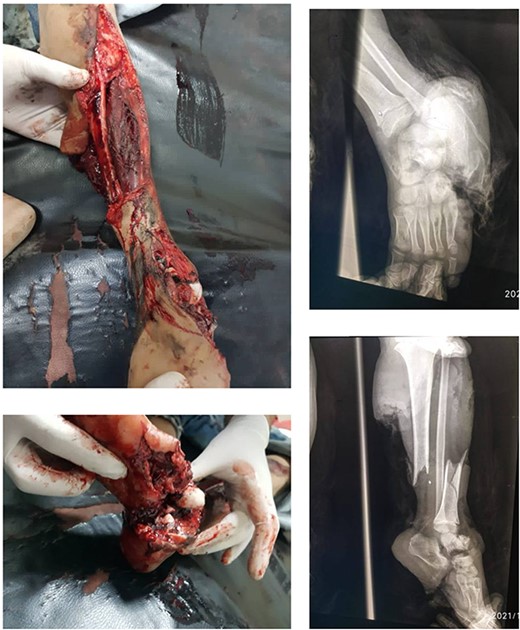

The decision to perform limb salvage surgery was made despite parental refusal and the consideration of the patient’s age. Initial debridement was performed in the supine position, with dislocations and fractures reduced and fixed using K-wires (Fig. 2). A temporary skewer was placed between the foot and the leg components to ensure stability. The patellar tendon, posterior muscles, and skin flap were meticulously sutured (Fig. 3). Postoperative follow-up showed satisfactory capillary refill, moderate sensation, and return of the anterior tibial artery pulse within three days. Progressive wound healing was observed over a month, allowing partial weight-bearing ambulation at 2 months (Fig. 4). Complete leg bone healing was achieved at 6 months, with removal of the flexible nail and restoration of the full range of motion and sensation (Fig. 5).

Displays the leg after suturing the skin flap, along with the X-ray image following the installation of the K-wires.